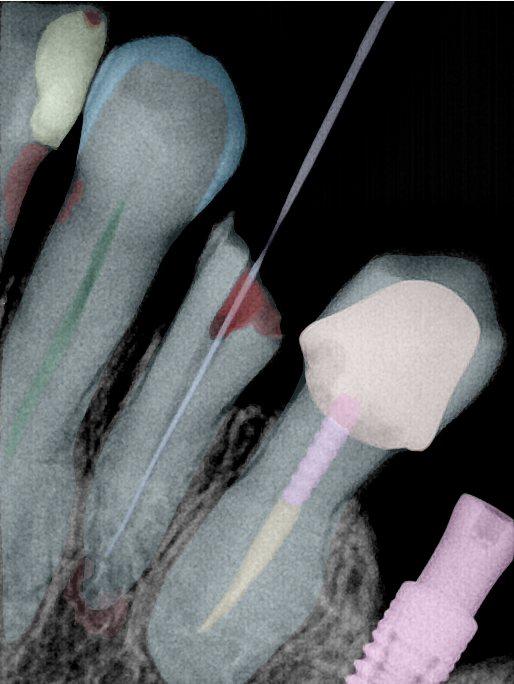

CR/DR 牙齿分割阶段记录

当前进展

- 完成了 CR/DR 牙齿相关分割训练

- 当前结果已经达到阶段预期,但仍有细节问题需要继续处理

相关测试

遇到的问题

- 训练过程中出现过 mask 下移问题

- 部分结果会出现 box 填充异常

- mask 边缘仍然有比较明显的锯齿感